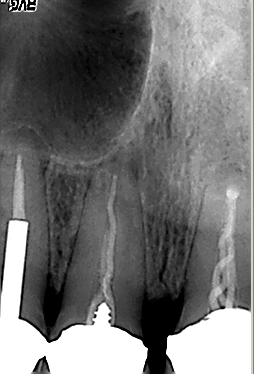

Röntgenologischer Ausgangsbefund im September. 2002 mit alio loco durchgeführter WF. Beide Wurzeln weisen eine apikale Parodontitis auf. Auch in der Furkation ist eine deutliche Resorption zu erkennen. Der Patient hat massive Schmerzen und einen stark herabgesetzten Allgemeinzustand